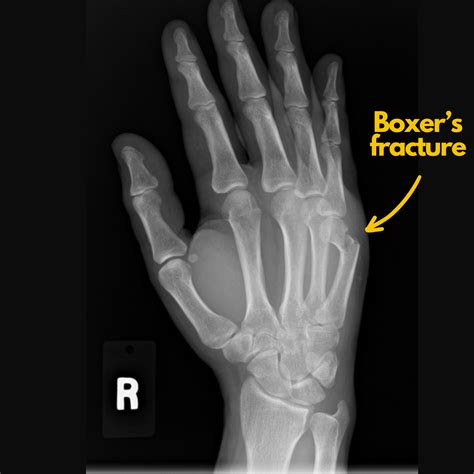

• boxer's fracture treatment at home

• what is a boxer's fracture

• boxer fracture treatment protocol

• closed boxer's fracture

• boxers hand fracture recovery time